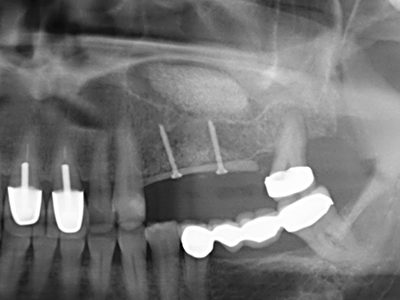

Die Präparation des lateralen Fensters bei der externen Sinusbodenelevation stellt gerade für chirurgisch unerfahrene Implantologen eine große Herausforderung dar. Die knöcherne Bedeckung der Kieferhöhle ohne eine Verletzung der darunterliegenden Schneider’schen Membran abzutragen ist dabei nur ein Teil der Operation – nach Schaffung eines ausreichenden Zugangs muss die Kieferhöhlenschleimhaut vorsichtig mobilisiert werden, um Raum für das einzubringende Material bzw. die Implantate zu schaffen. In dieser Indikation ist die Piezochirurgie zweierlei hilfreich: zum einen kann durch Verwendung diamantierter Instrumente eine selektive Knochenabtragung erfolgen und die darunter liegende Schleimhaut bleibt bei vorsichtiger Vorgehensweise intakt. Zum anderen unterstützen die Ultraschallfrequenzen zusätzlich eine komplikationslose Ablösung der Schleimhaut – sie werden durch spezielle stumpfe Ansätze in den Spaltraum zwischen Schleimhaut und Kieferhöhlenboden übertragen (Cassetta, Ricci et al. 2012, Pereira, Gealh et al. 2014) (Rickert, Vissink et al. 2013). So erscheint es nicht verwunderlich, dass in aktuellen Übersichtsarbeiten über die externe Sinusbodenelevation neben der Verwendung von rauen Implantatoberflächen und dem Einsatz von Knochenersatzmaterialien auch der Einsatz von piezoelektronischen Geräten als positiv bewertet wird (Wallace, Tarnow et al. 2012).